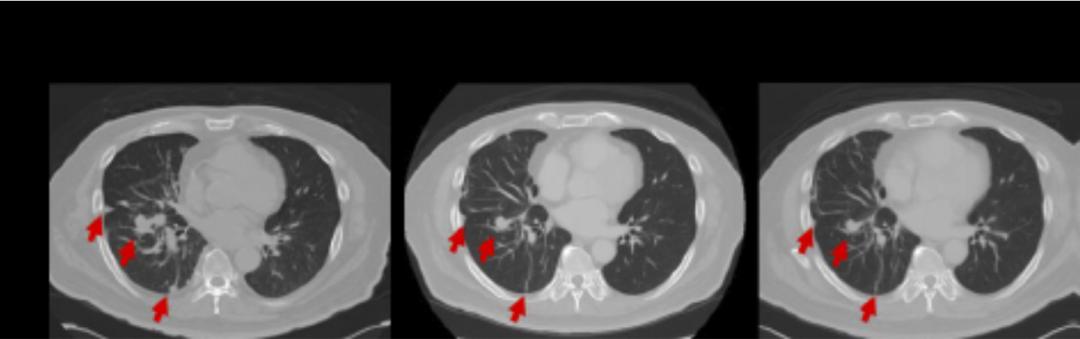

在治疗后不久,患者的血清癌胚抗原(CEA)和CA-125显著下降。4个月时随访,胸部CT扫描显示肿瘤大幅度缩小,达到部分缓解 (图3)。因此患者继续接受曲美替尼治疗,直到2020年5月胸部CT扫描证实疾病进展,无进展生存期7.4个月。

图3 曲美替尼治疗前后CT扫描